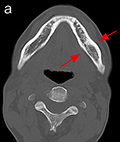

a:下顎骨C

図❷ CT画像では、左側下顎骨体部と左側鎖骨胸骨端の骨髄にhigh density areaを認める。MRI画像で同部の骨髄は、STIRで高信号を呈する

画像所見:パノラマX線写真では、67部の下顎骨体部に淡いすりガラス様のX線不透過像が認められた(図❶)。CT画像では、左側下顎骨体部の骨髄に high density area を認め、また、左側鎖骨胸骨端にも同様の像が認められた。MRI画像で同部の骨髄は、T1W1で低信号、STIRで高信号を呈していた(図❷)。